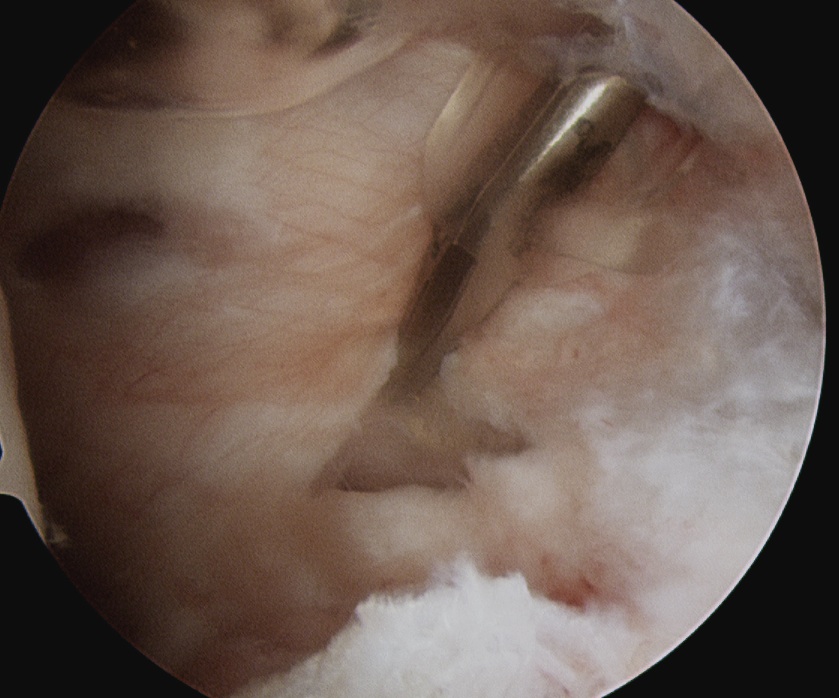

Arthroscopic Technique

Beachchair

- camera in lateral subacromial portal

- shaver in anterolateral portal

- identify coracoacromial ligament and follow to base of coracoid

- medial to this is fatty area with transverse humeral ligament

- identify the conoid ligament attaching to the base of the coronoid

Coracoacromial ligagment (CAL), coracoid and fatty area medial to coracoid

Insert suprascapular portal / accessory Neviaser portal

- behind posterior edge of acromion and anterior to spine of scapular

- insert blunt instruments under clavicle, and use to dissect fatty area

- identify suprascapular artery passing over the top of the transverse scapular ligament

- divide transverse scapular ligament through Neviaser portal while retracting suprascapular nerve

Conoid liagment and suprascapular artery (SSA) traveling over the transverse scapular ligament (TSL)

Division of the transverse scapular ligament (TSL) above the suprascapular nerve (SSN)